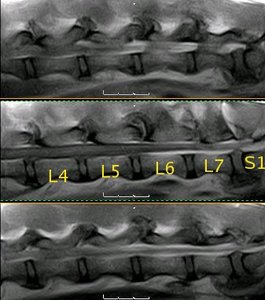

Resonancia magnética lumbo-sacra de pastor alemán |

La médula espinal acaba en L5, donde empieza la cola de caballo |